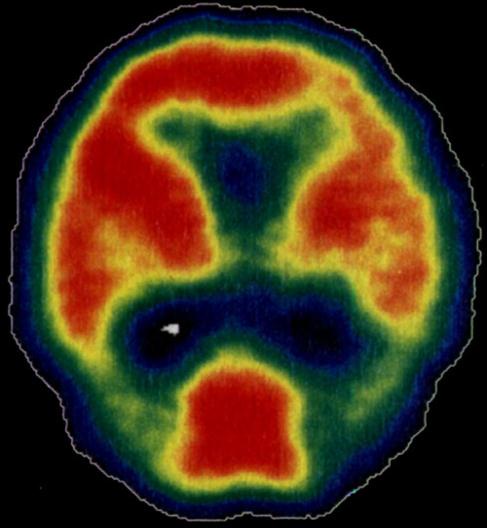

- Second, ACTRA aims to use innovative and advanced imaging techniques to better understand the link between cardiovascular risk, neurophysiology, and imaging markers of brain structure and function, and dementia related neuropathology cognitive decline as part of vascular and Alzheimer's dementia. For example, some of the projects will focus on cardiovascular and cerebrovascular link through neuroimaging methods such as MRI, SPECT (see figure below) and PET as well as researching the best methods of image analysis and of modelling imaging and other data.